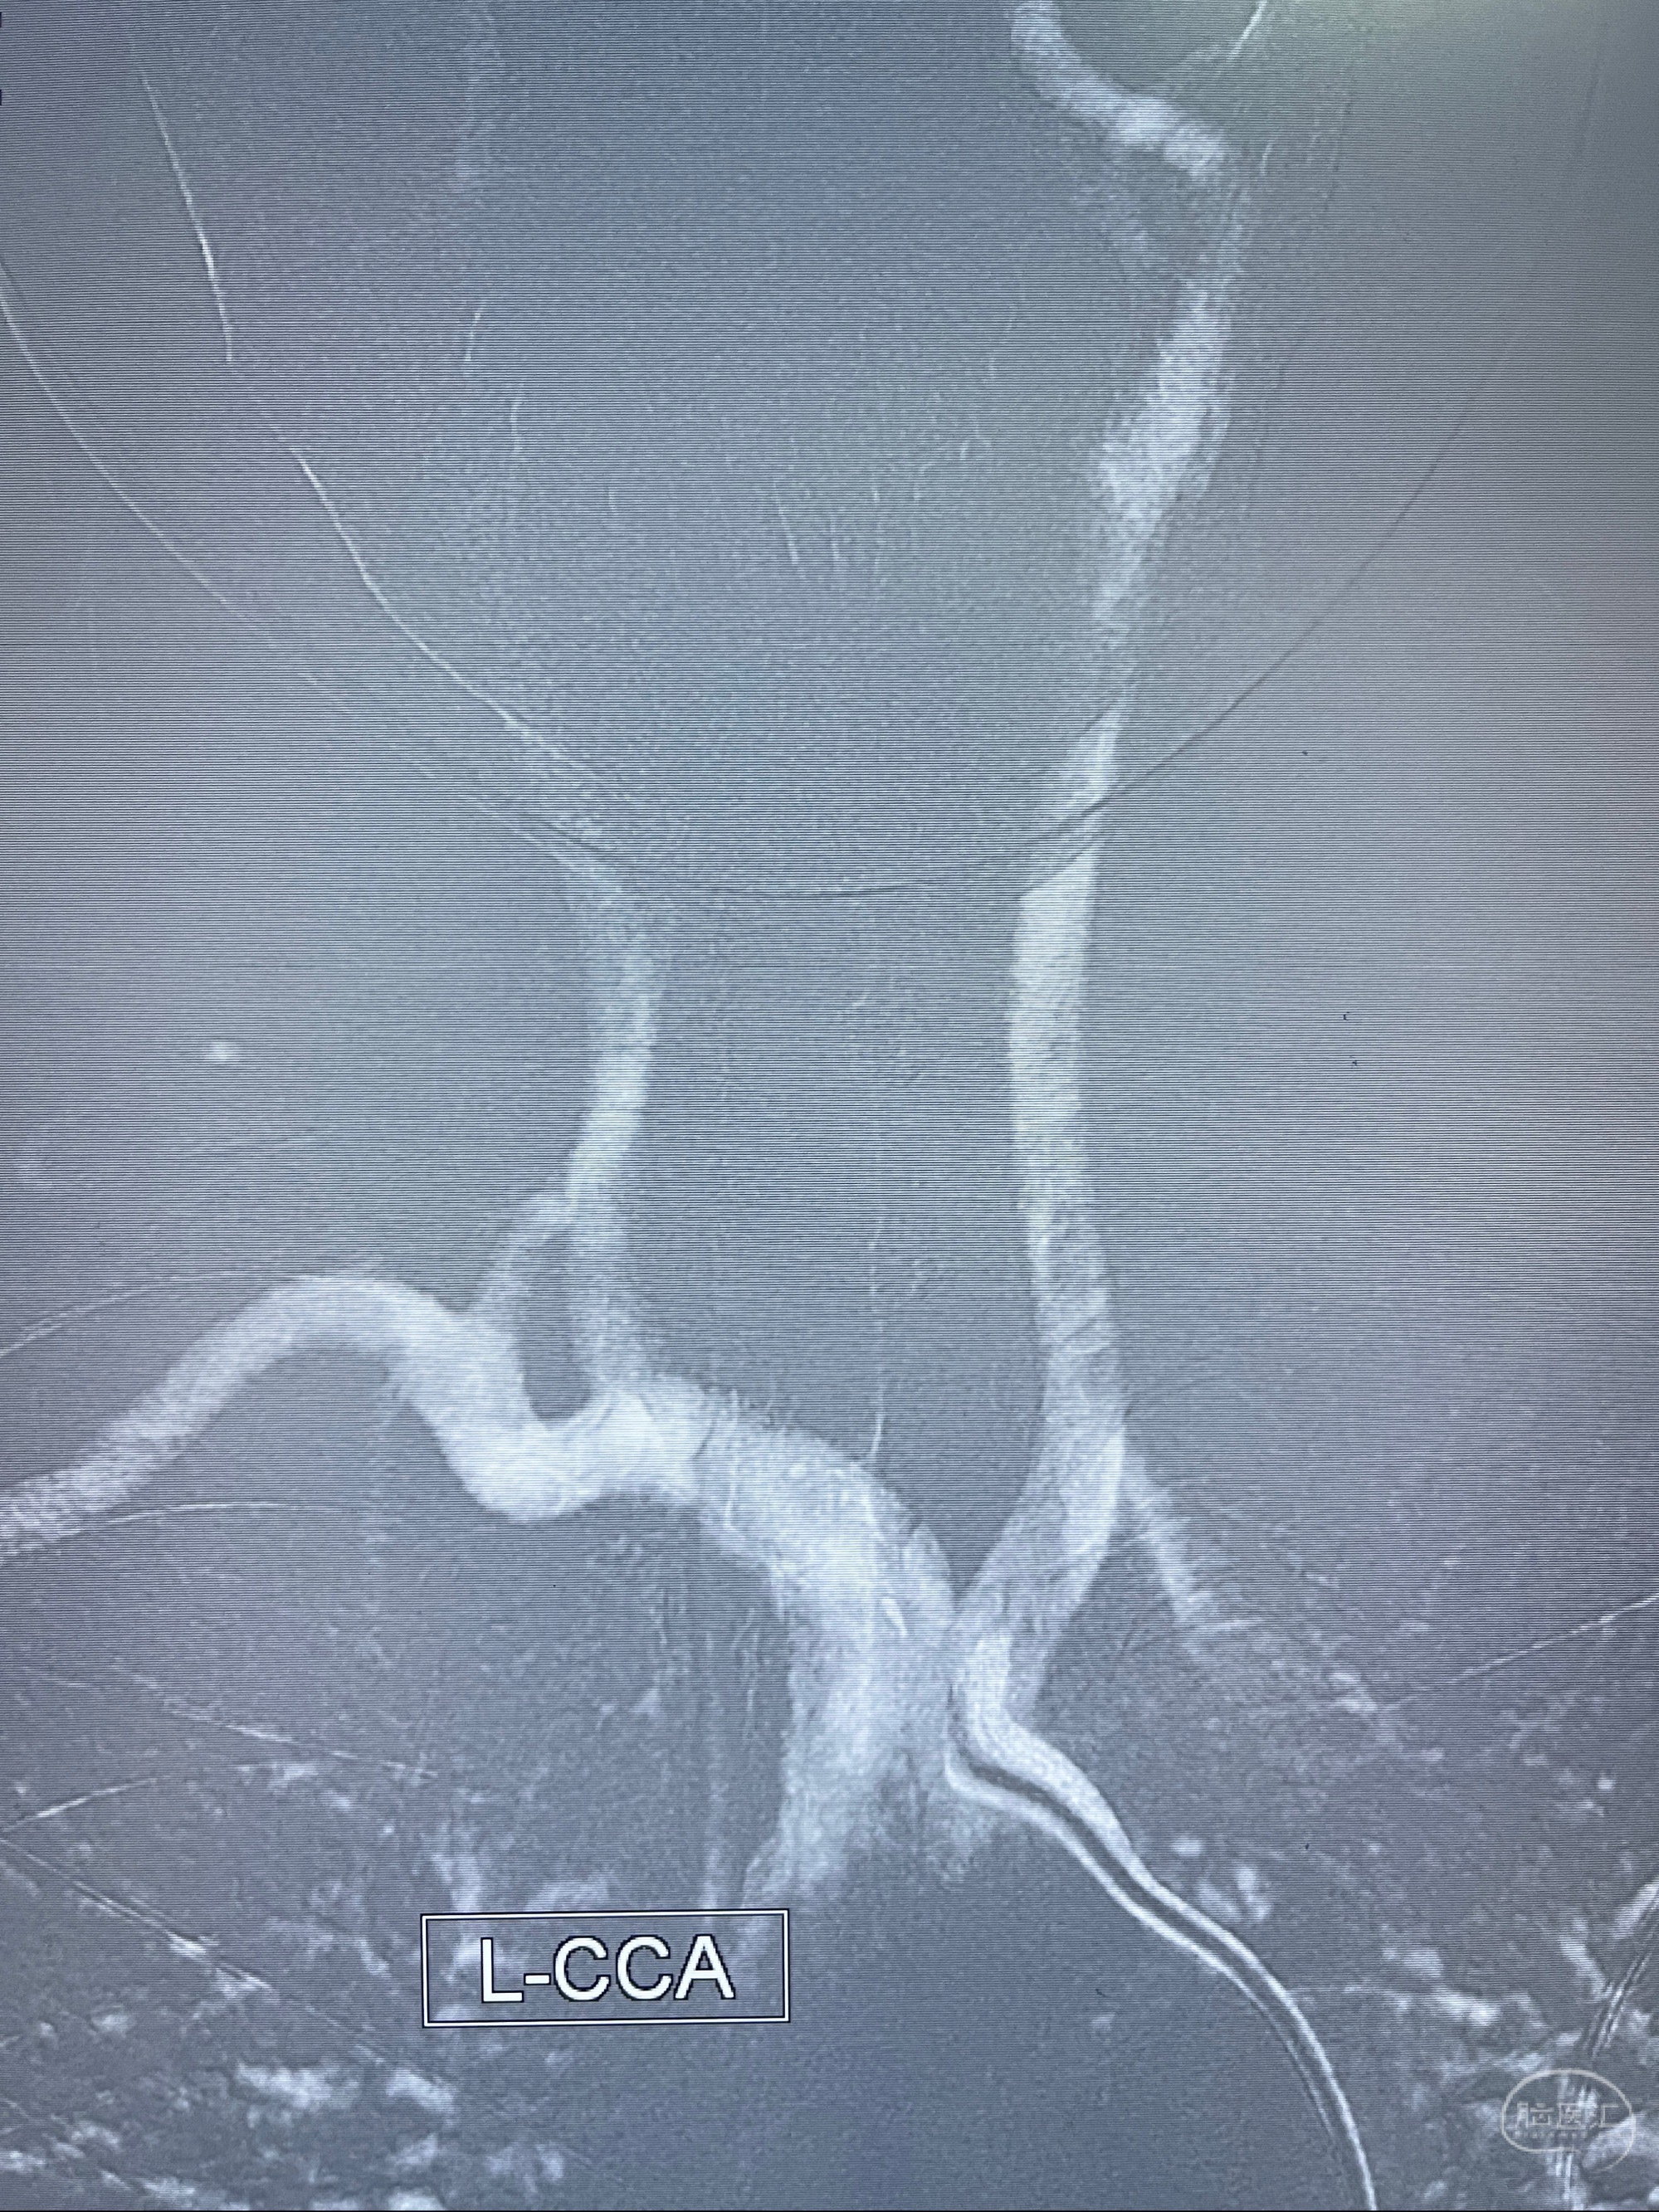

2023-08-14DSA:

左侧大脑中动脉动脉瘤,约2.6-2.8-3.4-2mm大小(瘤颈部、瘤体部、瘤高)

1.左侧大脑中动脉动脉瘤,约2.6-2.8-3.4-2mm大小(瘤颈部、瘤体部、瘤高)

2.外科手术夹闭or介入支架辅助栓塞